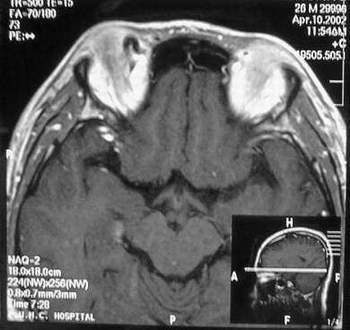

MRI及增强结果如下:

患者压颈及其它Valsava试验结果阴性。从MRI分析,在T1、T2、T+C检查该支血管均为明显流空现象,说明该血管血流速度很快,而从走行和分布看,眼上静脉可能性很大。也许也不能除外异常的眼动脉或异常血管。眶内主要可能的血管病变包括颈内动脉海绵窦瘘(高流窦)、AVM、眼眶静脉曲张、海绵状血管瘤、静脉性血管瘤、毛细血管瘤和眶内动脉瘤。。

1、颈内动脉海绵窦瘘:该患者临床有一部分支持该诊断。但从影像分析,海绵窦未见明显扩张;眼外肌未见明显充血扩张的长T1、长T2信号;颈内动脉海绵窦瘘常可见继发到血栓,可见到短T1、长T2的血栓信号。

2、眼眶静脉曲张:该疾患一般常见于小儿。该患大多数会出现Valsava试验阳性,间歇性突眼。不符合该患。影像学检查,于曲张静脉内常可见血栓和静脉石。所以不符合该患。

3、AVM:患者目前的影像学资料尚不全面,但可符合该诊断。临床上改病常见于30岁左右年轻人,单侧发病,于本患较符合。问题在于临床没有明确的血管杂音,似乎难以解释。

4、该患影像学与海绵状血管瘤差别很大,所以可基本排除此诊断。

5、静脉性血管瘤和毛细血管瘤:MRI中等T1、长T2信号,较易与本病鉴别。

6、眶内动脉瘤:我觉得患者并不能排除本病,但同样,由于波动性阴性,似乎也难以解释。

纵上所述:本人觉得,患者AVM可能性较大,同时不能除外眶内动脉瘤。